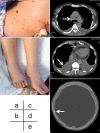

Thrombocytopenia, anasarca, fever, reticulin fibrosis, organomegaly (TAFRO) syndrome is a unique clinicopathologic subtype of multicentric Castleman's disease that has recently been identified in Japan. However, little is known about its renal histological changes and the optimal treatment for TAFRO syndrome. An 80-year-old Japanese woman was admitted to our hospital for evaluation of severe anasarca and weight gain (10 kg in a month). She had polyneuropathy, monoclonal plasma cell proliferative disorder with positive kappa M-protein, a sclerotic bone lesion, elevation of vascular endothelial growth factor (VEGF), skin changes, and extravascular volume overload, which fulfilled the diagnostic criteria for POEMS (polyneuropathy, organomegaly, endocrinopathy, and monoclonal protein, skin changes) syndrome. However, kappa-type M-protein and thrombocytopenia with positivity of platelet-associated immunoglobulin G antibody were unusual, and fitted the diagnostic criteria for TAFRO syndrome. Renal biopsy showed diffuse endocapillary proliferative glomerulonephritis with endothelial swelling and the infiltration of monocytes and neutrophils without specific immunoglobulin deposits. Her systemic symptoms were refractory to initial treatment with high-dose melphalan and glucocorticoids. Alternative therapy with an anti-interleukin-6 (IL-6) receptor antibody (tocilizumab) effectively controlled the symptoms, while a thrombopoietin receptor agonist (romiplostim) was effective for her thrombocytopenia. Results suggest that IL-6-VEGF axis and an autoimmune mechanism may be responsible for TAFRO syndrome with clinical features of POEMS and refractory thrombocytopenia, which can be successfully treated with combination of tocilizumab and romiplostim.